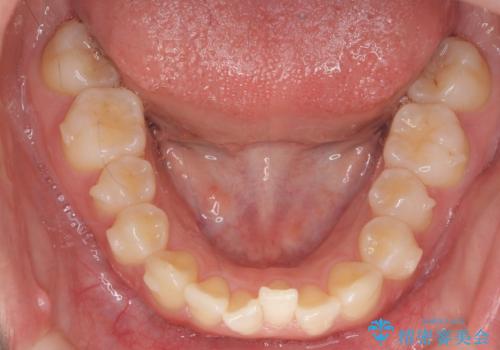

- 前歯のねじれを主訴に来院。

年齢が10代なこともあり、歯の動きは非常によく、リファインメントなしできれいに並びました。

下の前歯を少し削合して並べています。